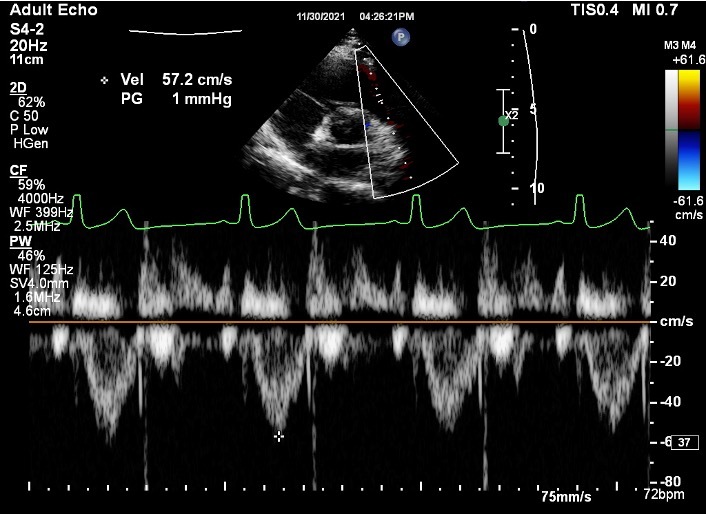

What should we remember when we get a PSAX TV CW clip? 3

A

1. Place the cursor through centre of TR jet, TV coaptation zone if no TR

2. Baseline 1/4 from top with 2.4 m/sec below baseline even if no TR is seen

3. Measure if parabolic jet seen